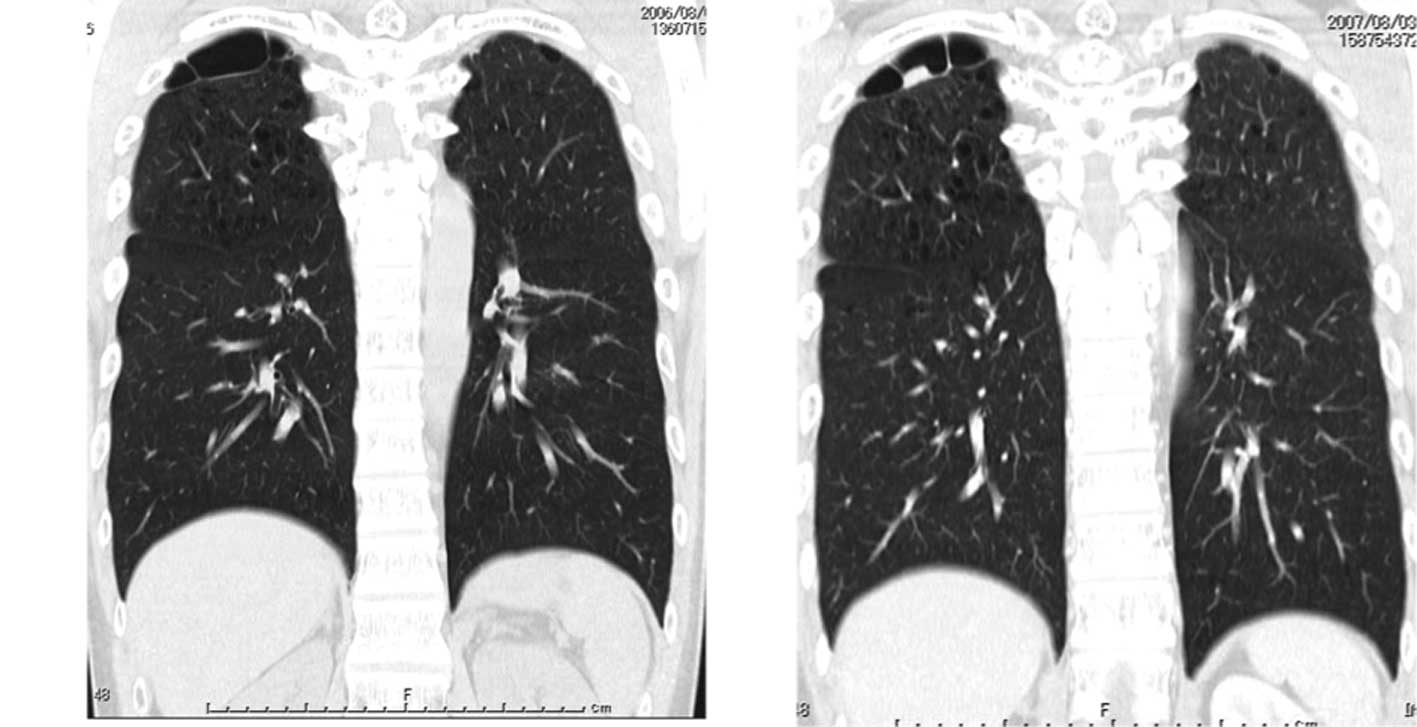

Lung Cancer And Interstitial Lung Diseases A Systematic Review